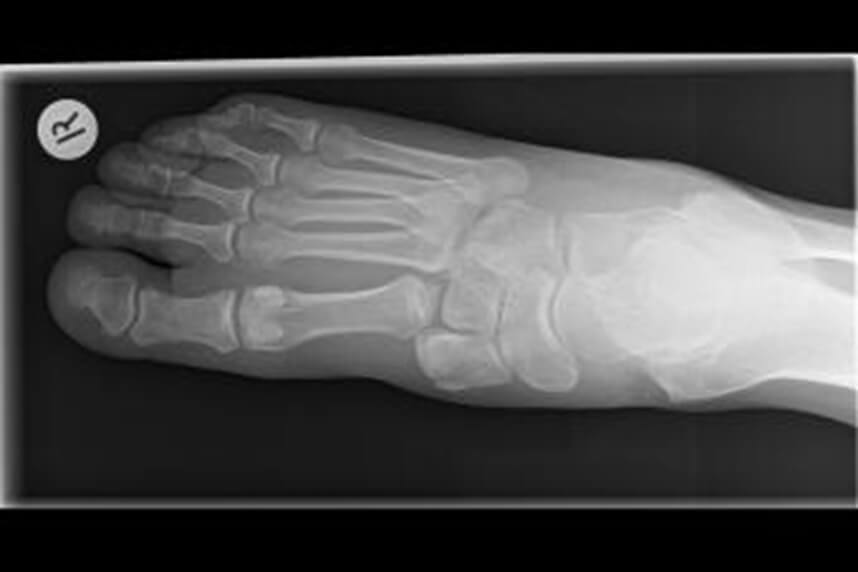

Fractura metatarsului

Fracturile metatarsului patru si cinci sunt cele mai comune si de obicei nu necesita operatie. Pacientii prezinta de obicei durere, urmare a unei luxatii sau dupa o cadere ori saritura. Accidentele de motocicleta sau masina sunt de asemenea responsabile de aceste rani.

Cursul normal de tratament implica imobilizarea piciorului cu un ghips pentru aproximativ 30 de zile, timp in care atrofia musculara in picior va fi evidenta. Si de aceasta data, radiografiile sunt extrem de importante pentru diagnostic. Din momentul in care terapeutul a verificat consolidarea fracturii si juxtapunerea corecta a capetelor osoase, reabilitarea poate incepe.

Programul de reabilitare va debuta cu o incarcare foarte usoara si va progresa constant pana cand nu vor mai fi necesare carjele. Inainte ca reabilitarea pe teren sa poata incepe, pacientul trebuie sa aiba o gama larga de miscari, fluiditate, proprioceptie si o forta musculara buna in membrul inferior.

Daca au fost folosite tehnici de osteosinteza, programul de reabilitare nu se schimba semnificativ, totusi exercitiile cu rezistenta pot incepe mai devreme, reducand durata totala a procesului.